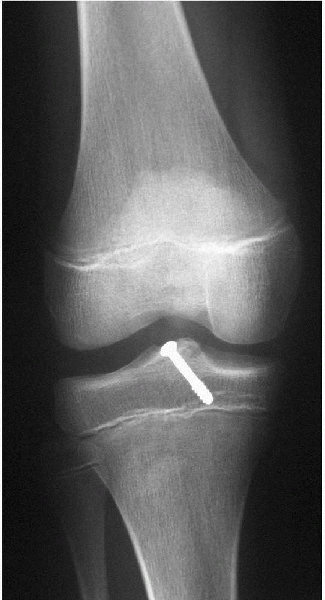

This can be done open or arthroscopically with predictable healing in 6 weeks (Fig. 5-9).

![]() |

Figure 5-9

Repair of a type III tibial spine avulsion. Most surgeons are using arthroscopic means and avoiding the physis. Comminuted fractures can be repaired with suture through holes made with the ACL tibial tunnel guide. |

Patellofemoral Stress Syndrome